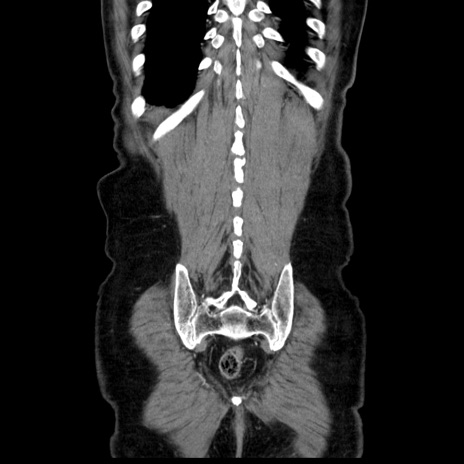

横断像